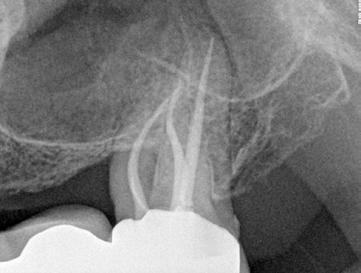

FQ . Clinical Case.

Dr. David Christofzik Specialist for endodontics and traumatology, Kiel /Germany

Rafael Michiels

for endodontics

“FQ allows general practitioners to proceed with a great deal more security and confidence, whereas the high versatility of the instruments enables specialists to respond individually to complicated canal anatomies, as shown in the patient case.”